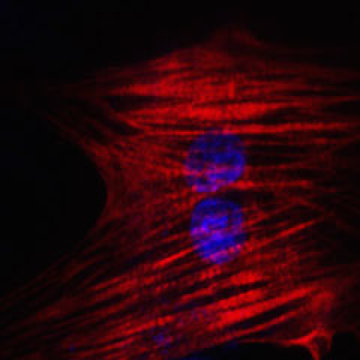

Célula del corazón reprogramada a partir de una célula de la piel. Imagen: Nan Cao. Fuente: Institutos Gladstone.

En el estudio de Science, dirigido por el primer autor Nan Cao, postdoc en el laboratorio de Ding, los investigadores utilizaron un cóctel de nueve productos químicos para transformar las células de piel humana en células del corazón. Por ensayo y error, encontraron la mejor combinación de productos químicos para comenzar el proceso, cambiando las células a un estado parecido al de las células madre multipotentes, que pueden convertirse en muchos tipos diferentes de células en un órgano en particular.

Un segundo cóctel de sustancias químicas y factores de crecimiento ayudó a las células a convertirse en células musculares del corazón.

Con este método, más de 97% de las células comenzaron a latir, una característica de las células del corazón completamente desarrolladas y sanas. Las células también respondieron apropiadamente a las hormonas, y molecularmente, se parecían a las células del músculo del corazón, no a las células de la piel. Es más, cuando las células fueron trasplantadas a un corazón de ratón al inicio del proceso, evolucionaron a células musculares del corazón de aspecto saludable.